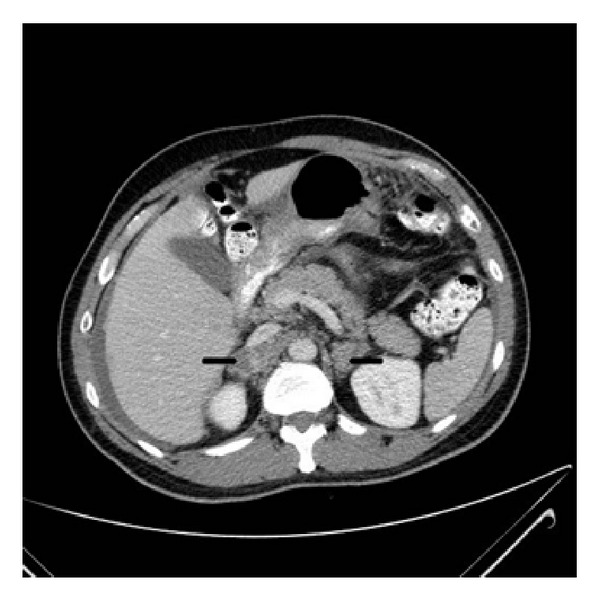

Pre-training data. We use the same dataset as LLaVA-Med (llava-med). Stage 1 includes 600K image-text pairs filtered from PMC-15M, converted into instruction-following data with simple image descriptions. Stage 2 comprises 60K image-text pairs from PMC-15M across five modalities: CXR, CT, MRI, histopathology, and gross pathology. GPT-4 is then employed to generate multi-round Q&A in a tone mimicking visual interpretation, converting these pairs into an instruction-following format.